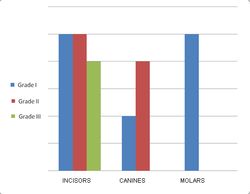

48% of the teeth analyzed showed grade I occlusal/incisal wear, 36% showed grade II wear and the remaining 16% showed grade III wear, according to the modified Gerasimov’s scale (Fig. 9). The wear on the proximal surfaces of all groups of teeth was classified as grade I.

Fig. 9. Tooth wear distribution (occlusal/incisal) according to the modified Gerasimov’s scale

48% of the teeth analyzed showed grade I occlusal/incisal wear, 36% showed grade II wear and the remaining 16% showed grade III wear, according to the modified Gerasimov’s scale (Fig. 9). The wear on the proximal surfaces of all groups of teeth was classified as grade I.

Fig. 9. Tooth wear distribution (occlusal/incisal) according to the modified Gerasimov’s scale